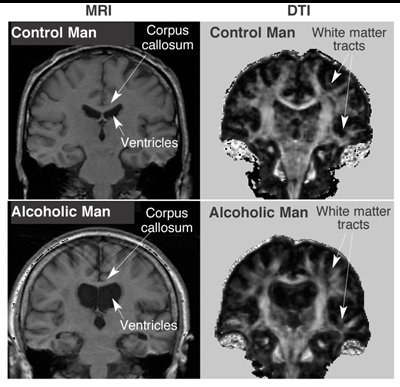

الحاله تسمى Wernicke encephalopathy

وهي عباره عن حاله تحدث بسبب شرب الكحول لفترات طويله مما يؤدي إلى نقصان فيتامين ب1 (Thiamin)الذي يعتبر عنصر اساسي لتحلل السكر داخل الجسم واستخدامه كطاقه.